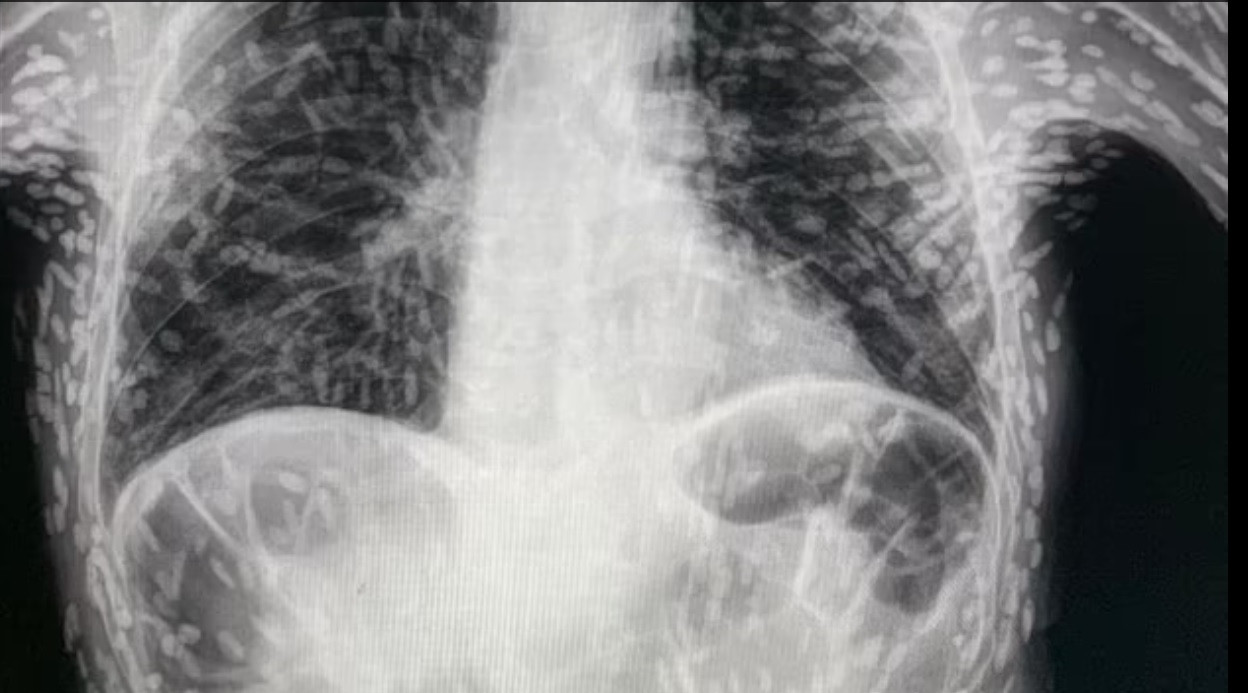

Un pacient care avea o tuse persistentă a descoperit că avea un parazit intestinal, în urma unei radiografii cu raze X, relatează Daily Mail.

După ce s-a prezentat la spital, acesta a descoperit că în stomacul său există rămășițele unui parazit. Teniaza este o infecție cauzată de ingerarea de mâncare sau lichide contaminate cu ouă sau larve de tenie.

Un medic din Botucatu, cel care a publicat radiografia pacientului pe Twitter, recomandă oamenilor ca alimentele să fie bine spălate înainte de a fi consumate, pentru a preveni astfel de infecții.

„Cisticercoza este dobândită prin ingerarea de ouă de tenie. Spălați-vă bine alimentele înainte de a le consuma! Dacă nu aveți nicio afecțiune a creierului, măduvei spinării sau ochilor, nici măcar nu trebuie să vă tratați. Aceste leziuni sunt calcificate, astfel încât nu sunt cisticerci viabile (larve de tenie). Dacă nu provoacă niciun disconfort, viața continuă”, a precizat dr. Vitor Borin de Souza, medic la Spitalul das Clínicas din Botucatu.

Astfel de chisturi pot provoca, însă, moartea. Dacă durerile de cap și chiar convulsiile sunt frecvente, acești noduli pot duce, de asemenea, la confuzie, amețeli și o afecțiune numită hidrocefalie, un exces de lichid în creier, care - dacă nu este trataă la timp - poate fi fatală. În aceste cazuri, este necesară o intervenție chirurgicală pentru a elimina chisturile.